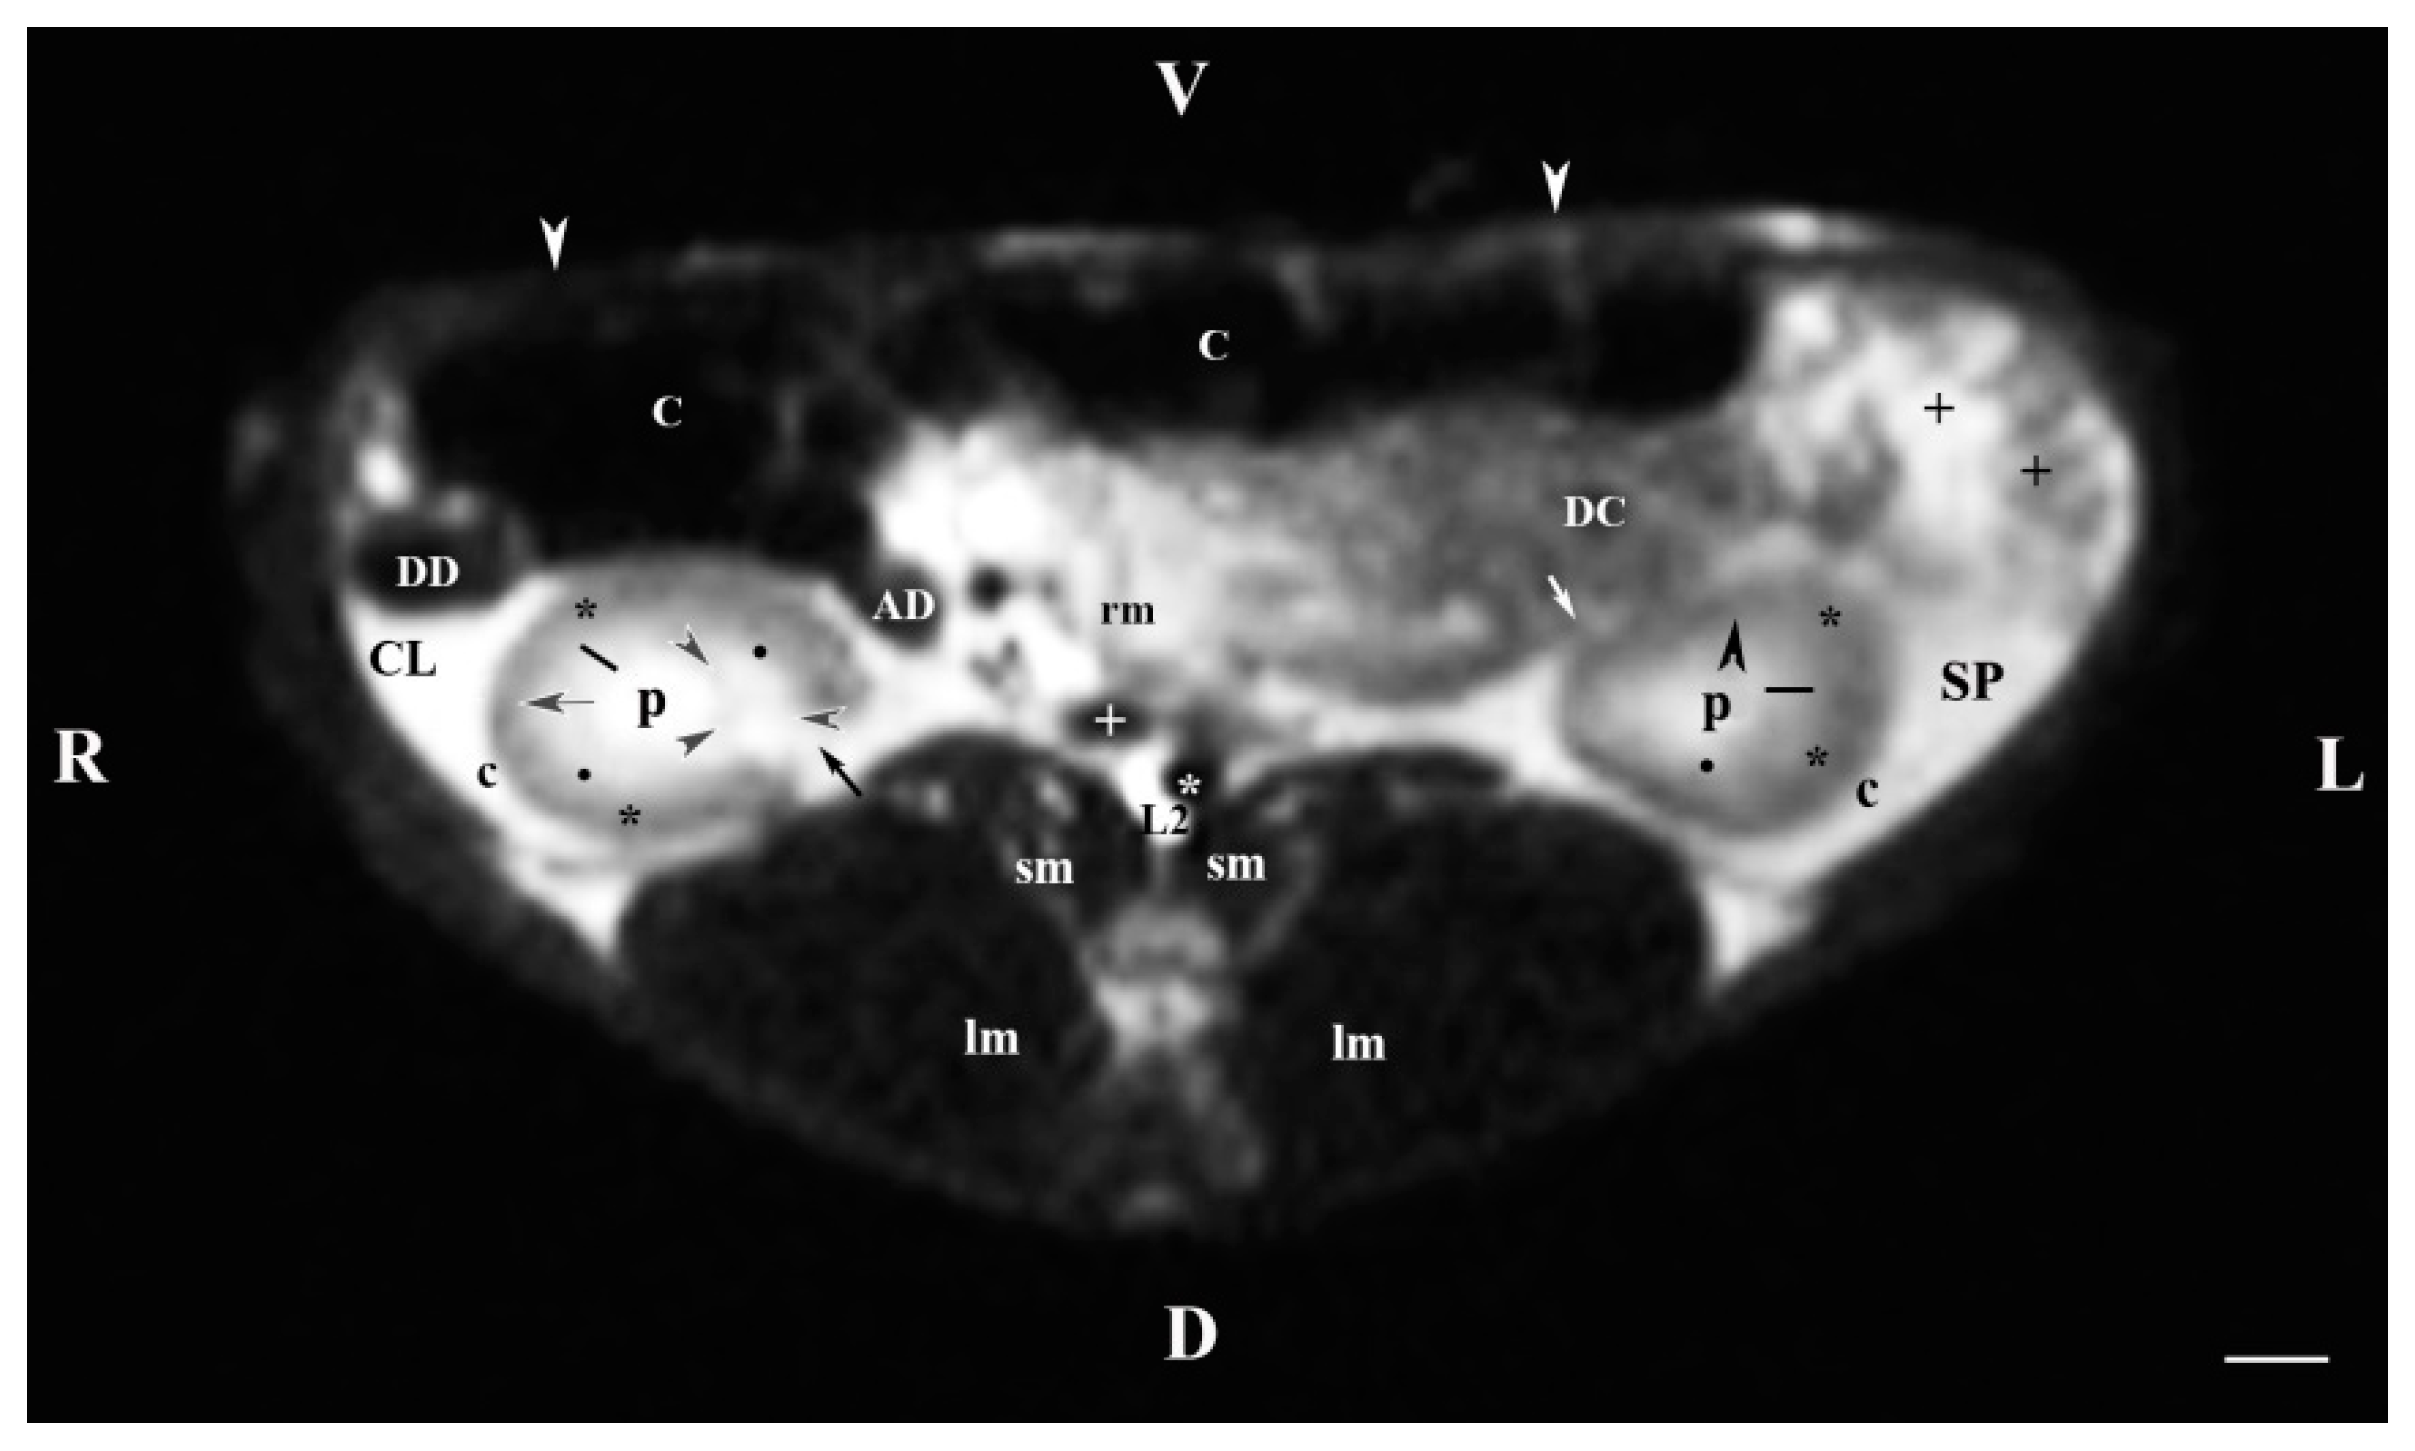

3.1. Transverse MRI